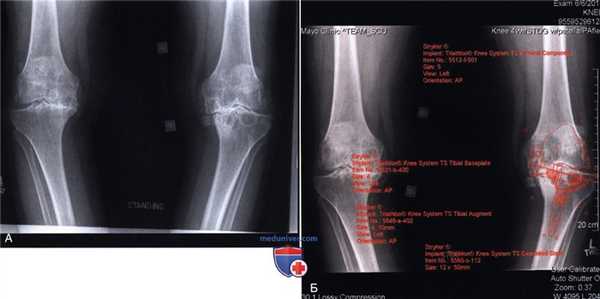

д) Полезным при предоперационном планировании будет предварительное определение размеров компонентов и глубины опилов с помощью шаблонов (рис. 3):

• Высота проксимального большеберцового опила

• Необходимость дополнительной аугментации медиального плато по выполнении опила

• Высота дистального опила бедра

• Возможные размеры имплантов.